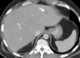

Avascular or hypovascular liver lesion

May Be Caused by